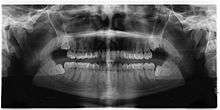

If the tooth cannot be assessed with clinical exam alone, the diagnosis is made using either a panoramic radiograph or cone-beam CT. Where unerupted wisdom teeth still have eruption potential several predictors are used to determine the chance of the teeth becoming impacted. The ratio of space between the tooth crown length and the amount of space available, the angle of the teeth compared to the other teeth are the two most commonly used predictors, with the space ratio being the most accurate. Despite the capacity for movement into early adulthood, the likelihood that the tooth will become impacted can be predicted when the ratio of space available to the length of the crown of the tooth is under 1.[3]:141

There is no standard to screen for wisdom teeth. It has been suggested, absent evidence to support routinely retaining or removing wisdom teeth, that evaluation with panoramic radiograph, starting between the ages of 16 and 25 be completed every 3 years. Once there is the possibility of the teeth developing disease, then a discussion about the operative risks versus long-term risk of retention with an oral and maxillofacial surgeon or other clinician trained to evaluate wisdom teeth is recommended. These recommendations are based on expert opinion level evidence.[17] Screening at a younger age may be required if the second molars (the "12-year molars") fail to erupt as ectopic positioning of the wisdom teeth can prevent their eruption. Radiographs can be avoided if the majority of the tooth is visible in the mouth.